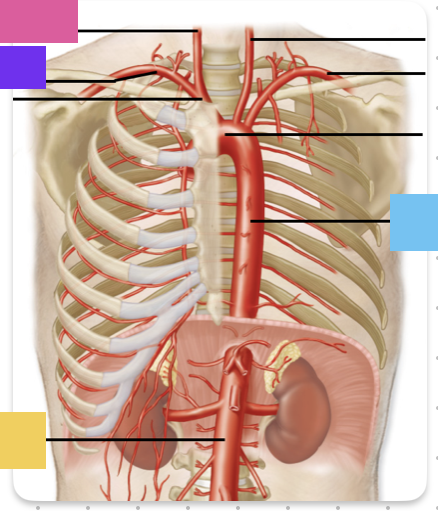

aortic arch

brachiocephalic trunk (blue)

right common carotid artery

right subclavian artery

left common carotid artery (grey)

left subclavian artery (black)

descending aorta

thoracic aorta

abdominal aorta